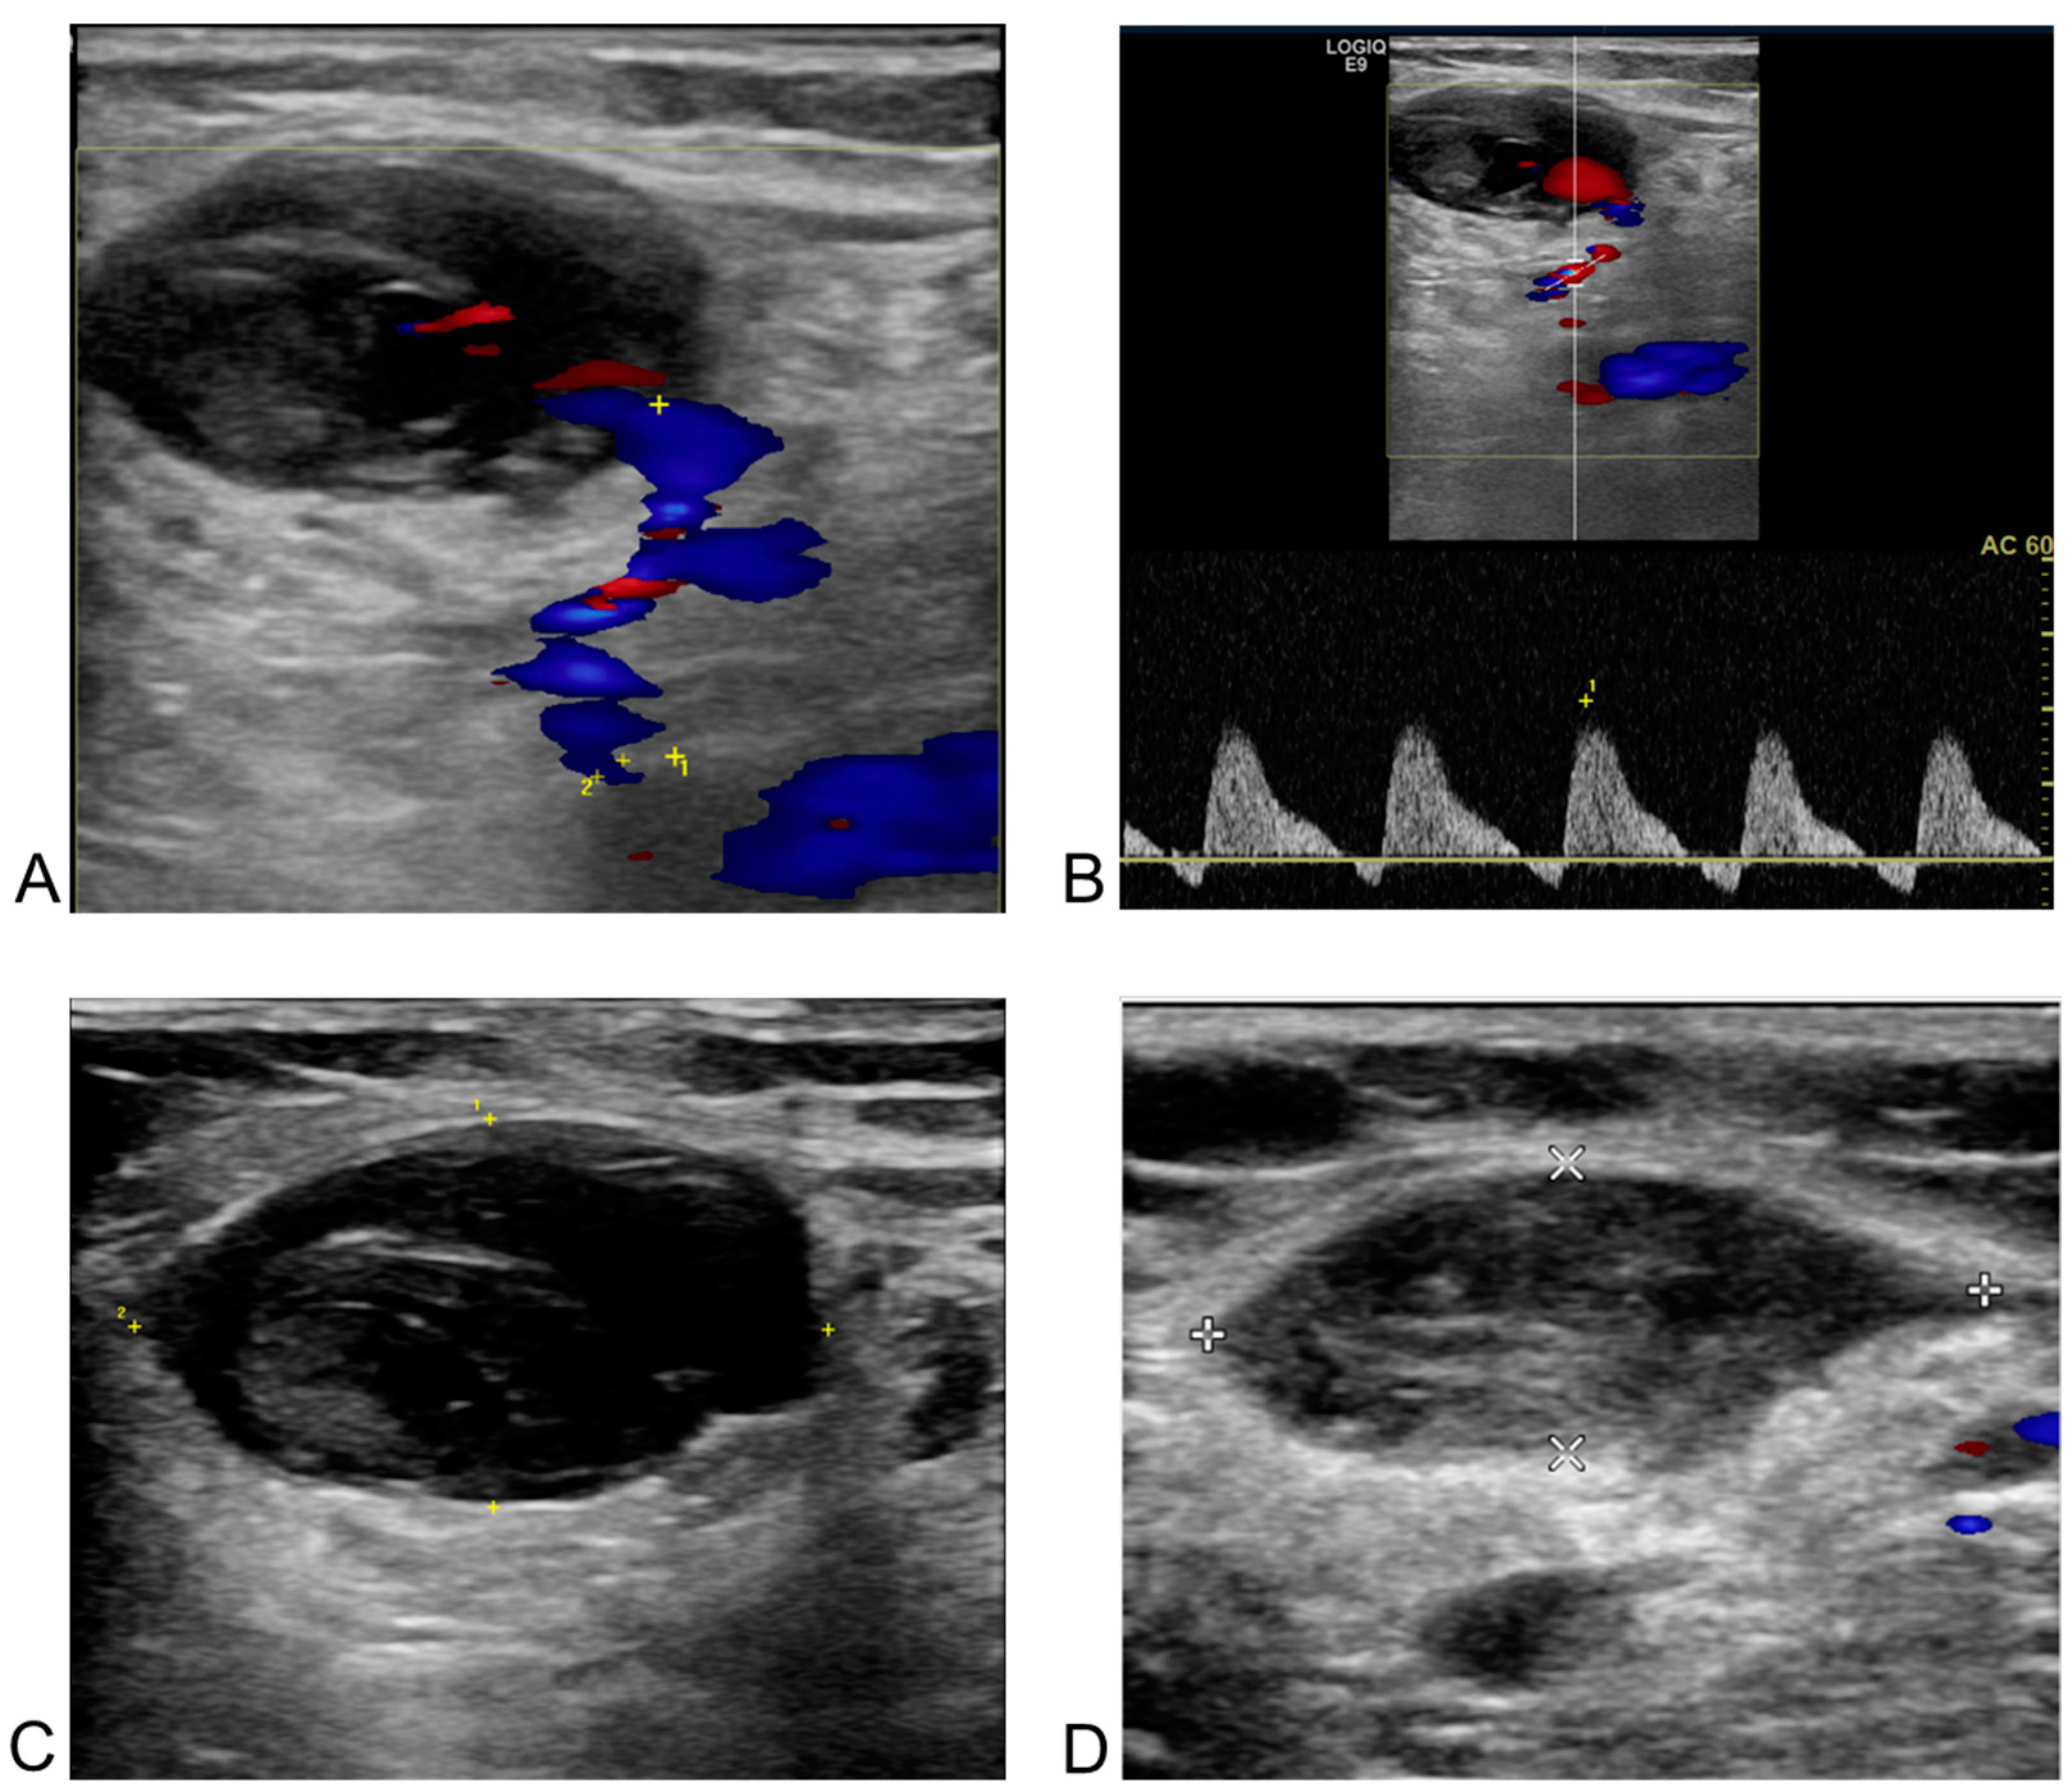

3.3. Incidence of Femoral Vascular Complications

3.4. Management of Femoral Vascular Complications

3.5. Follow-Up of Femoral Vascular Complications